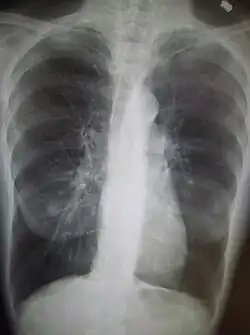

Rentgenový snímek hrudníku pacienta s CHOPN

Chronická obstrukční plicní nemoc (CHOPN, dříve chronická bronchitida) je systémové zánětlivé onemocnění, které postihuje hlavně dýchací soustavu. CHOPN je v současné době léčitelná, ale není vyléčitelná.